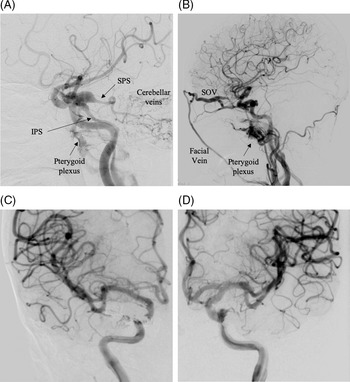

Diagnostic cerebral angiography demonstrated bilateral dCCFs, with the right being more severe than the left (Figure 2A,B). The right CCF drained predominantly via the superior and inferior petrosal sinuses (SPS, IPS). The left CCF drained mainly through the left SOV.

Figure 2: Diagnostic cerebral angiogram with bilateral common carotid injections (A, B) pre- and (C, D) post-coil embolization demonstrate: (A) Right ICA injection demonstrates a direct CCF with early shunting in the jugular vein and venous drainage via the petrosal sinuses, pterygoid plexus, and distension of cerebellar veins. (B) Left ICA injection demonstrates a left CCF with drainage into a distended SOV and superficial facial draining vein. (C, D) Successful treatment of bilateral direct CCFs via endovascular coil embolization and obliteration of the venous pathway. (IPS: inferior petrosal sinus, SOV: superior ophthalmic vein, SPS: superior petrosal sinus.)

Our case exhibited two distinct venous drainage patterns on each side. The right fistula drained posteriorly via the petrosal sinuses, which resulted in the dilation of the cerebellar veins and cerebellar symptoms. The patient also exhibited right-sided orbital and cavernous symptoms, and accordingly both CT and MR studies demonstrated bilateral SOV dilation. However, cerebral angiography did not show flow through the right SOV. These findings suggest possible spontaneous thrombosis of the right SOV, a feature that is a high risk for hemorrhage (Figure 2A). The patient’s only left-sided symptom was decreased visual acuity, consistent with congestion of the SOV (Figure 2B).